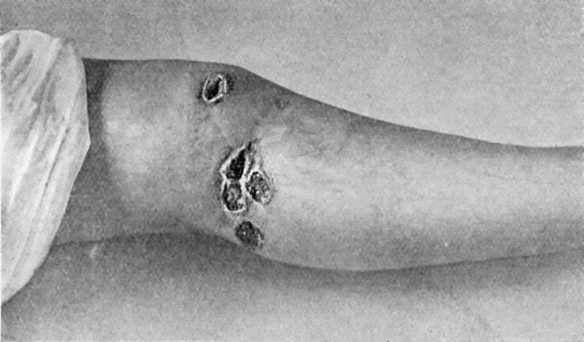

65 14.Leg Ulcers associated with Varicose Veins

71 15.Perforating Ulcers of Sole of Foot

74 16.Bazin's Disease in a girl æt. 16

75 17.Syphilitic Ulcers in region of Knee

76 18.Callous Ulcer showing thickened edges